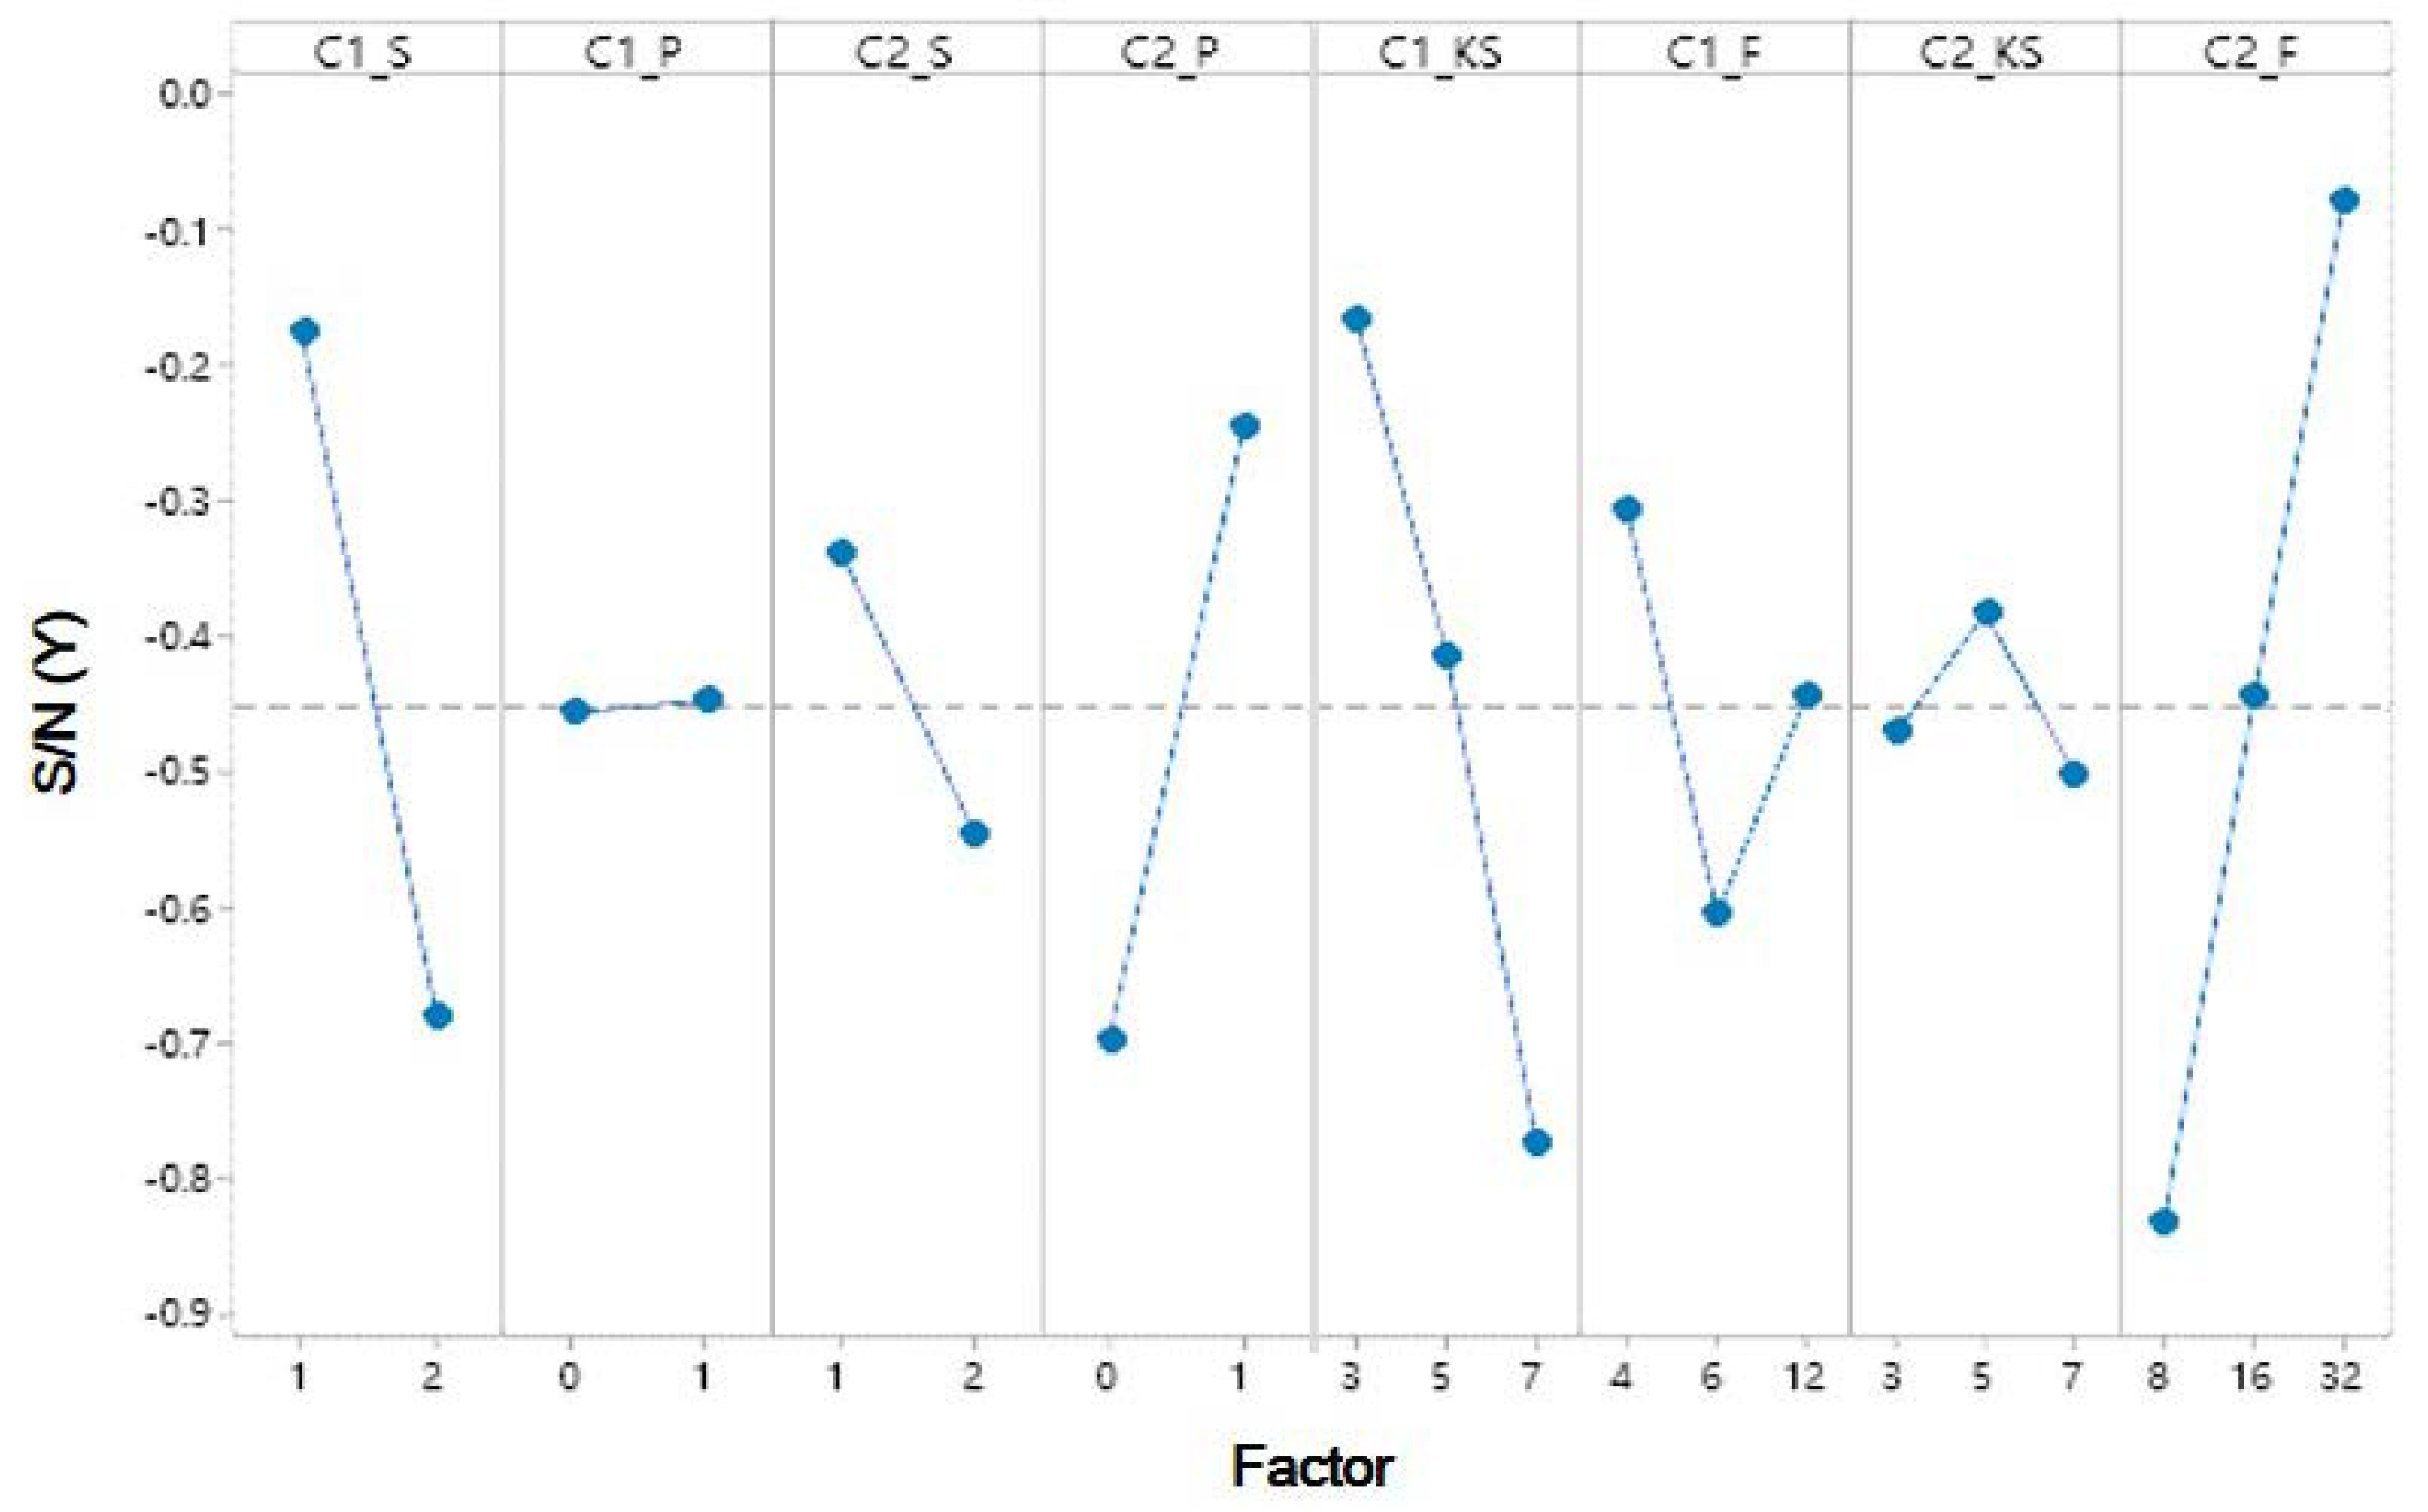

3.1. LIDC-IDRI

| Level | Factors | |||||||

|---|---|---|---|---|---|---|---|---|

| A C1_S | B C1_P | C C2_S | D C2_P | E C1_KS | F C1_F | G C2_KS | H C2_F | |

| 1 | −0.7002 | −0.7672 | −0.6953 | −0.9153 | −0.5467 | −0.6927 | −0.7514 | −1.199 |

| 2 | −0.8939 | −0.8381 | −0.898 | −0.7147 | −0.7258 | −0.8493 | −0.9297 | −0.8646 |

| 3 | −1.1451 | −0.8756 | −0.7365 | −0.354 | ||||

| Delta | 0.1938 | 0.0708 | 0.2028 | 0.2006 | 0.5985 | 0.1829 | 0.1933 | 0.845 |

| Rank | 5 | 8 | 3 | 4 | 2 | 7 | 6 | 1 |

| Best level | 1 | 1 | 1 | 2 | 1 | 1 | 3 | 3 |

| Optimal parameter | 1 | 0 | 1 | 1 | 3 | 4 | 7 | 32 |